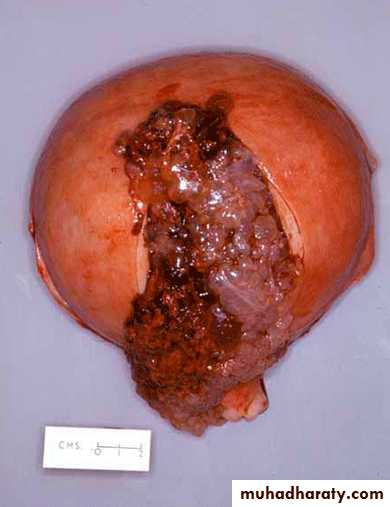

Hydatidiutiform mole appears as multiple vesicles as bunch of grapes in complete mole

Microscopical:complete mole

Generalized swelling of villous tissueDiffuse trophoblastic hyperplasia

No embryonic or fetal tissue

Absence of fetal blood vessel

The avascular villi of molar pregnancy are quite large. However, these must be distinguished from simple "hydropic degeneration" seen in placentas of fetuses undergoing intrauterine demise.